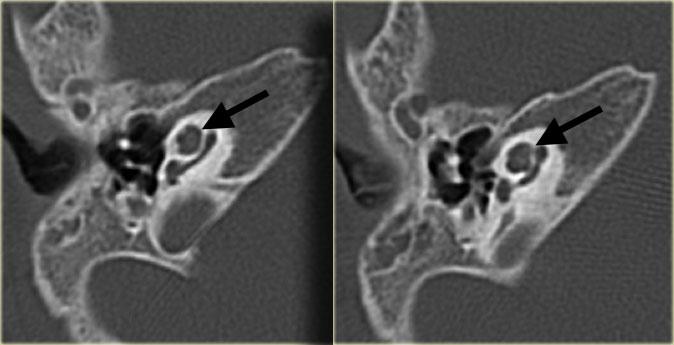

Bên trái là hình ảnh của một bé gái 2 tuổi.

Các hình ảnh từ kết quả chụp CT được thực hiện trước khi cấy ốc tai điện tử.

Quan sát thấy dị dạng nhẹ ở đỉnh ốc tai – không có sự phân tách giữa vòng thứ hai và vòng thứ ba, và trụ ốc tai xương vắng mặt.

Cống tiền đình bình thường.